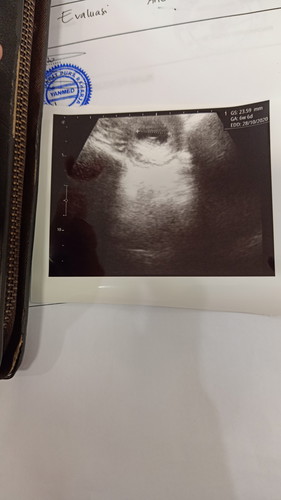

Saya sudah melakukan testpack dah hasilnya garis 2. Menurut perkiraan usia kandungan saya antar 10/11 minggu. Tetapi sudah 3 hari ini saya mengalami flek. Dan menurut dokter janin saya belum tampak hanya ada kantong rahimnya saja. Saat diusg juga seperti itu. Dan saya diminta datang lagi minggu depan dan diberi asam folat. Sya jd takut. Apakah ada yg mengalaminya juga? Apa ada yg memiliki solusi lain?

Bun tapi itu kata dokternya kenapa? Perkiraan 10minggu ya bun? Itu di print usg tertera 6minggu, semoga masih rejeki ya bun. Kalau boleh saran second opinion aja bun, cari dokter lain. Kalau mau jelas bisa usg transvaginal bun..

Ini usg 2d apa usg transvaginal bun? Soalnya saya tadi sore jg habis cek kandungan, 7 week di usg 2D tp belum terlihat janin, lalu di usg transvaginal janin terlihat dan sdh ada detak jantungnya..ukuran janin baru 0.59..